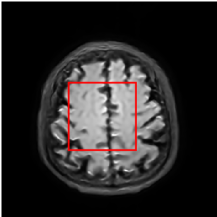

Figure 5 provides the qualitative comparison of the various methods on the four datasets at a scale of 4. The top, second, third, and bottom rows are the SR results under the FastMRI, clinical brain, clinical tumor and clinical pelvic datasets, respectively. The red boxes indicate the zoom-in region of complicated anatomical structures along with their corresponding error maps. Note that the brighter textures in the error maps, the lower the quality of the reconstructed images. As can be seen, compared to methods based on Transformers and CNNs, diffusion-based methods like DisC-Diff and DiffMSR (Ours) are capable of reconstructing high-realistic images with promising reconstruction metric scores (PSNR and SSIM). Nevertheless, while DisC-Diff can reconstruct high-precision MR images, it does not preserve the structure present in the original HR images, introducing some additional information that can affect medical diagnosis. In contrast, our method combines DM and PLWformer, which can preserve the original image’s structure while restoring high-frequency information.

In this section, we present more visual qualitative comparisons. Figures 8, 9, 10, and 11 show the reconstruction results of each method in FastMRI, clinical brain, clinical tumor, and clinical pelvic, respectively. As can be seen, although DisC-Diff can reconstruct MR images with high-frequency information, it fails to preserve the structure and content of the original Target HR image effectively, resulting in image distortion. In contrast, our proposed DiffMSR can restore high-frequency information while preserving the structure of the original HR image, indicating the effectiveness of the joint use of DM and PLWformer.